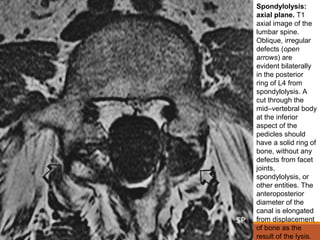

Spondylolysis:

axial plane. T1

axial image of the

lumbar spine.

Oblique, irregular

defects (open

arrows) are

evident bilaterally

in the posterior

ring of L4 from

spondylolysis. A

cut through the

mid–vertebral body

at the inferior

aspect of the

pedicles should

have a solid ring of

bone, without any

defects from facet

joints,

spondylolysis, or

other entities. The

anteroposterior

diameter of the

canal is elongated

from displacement

of bone as the

result of the lysis.